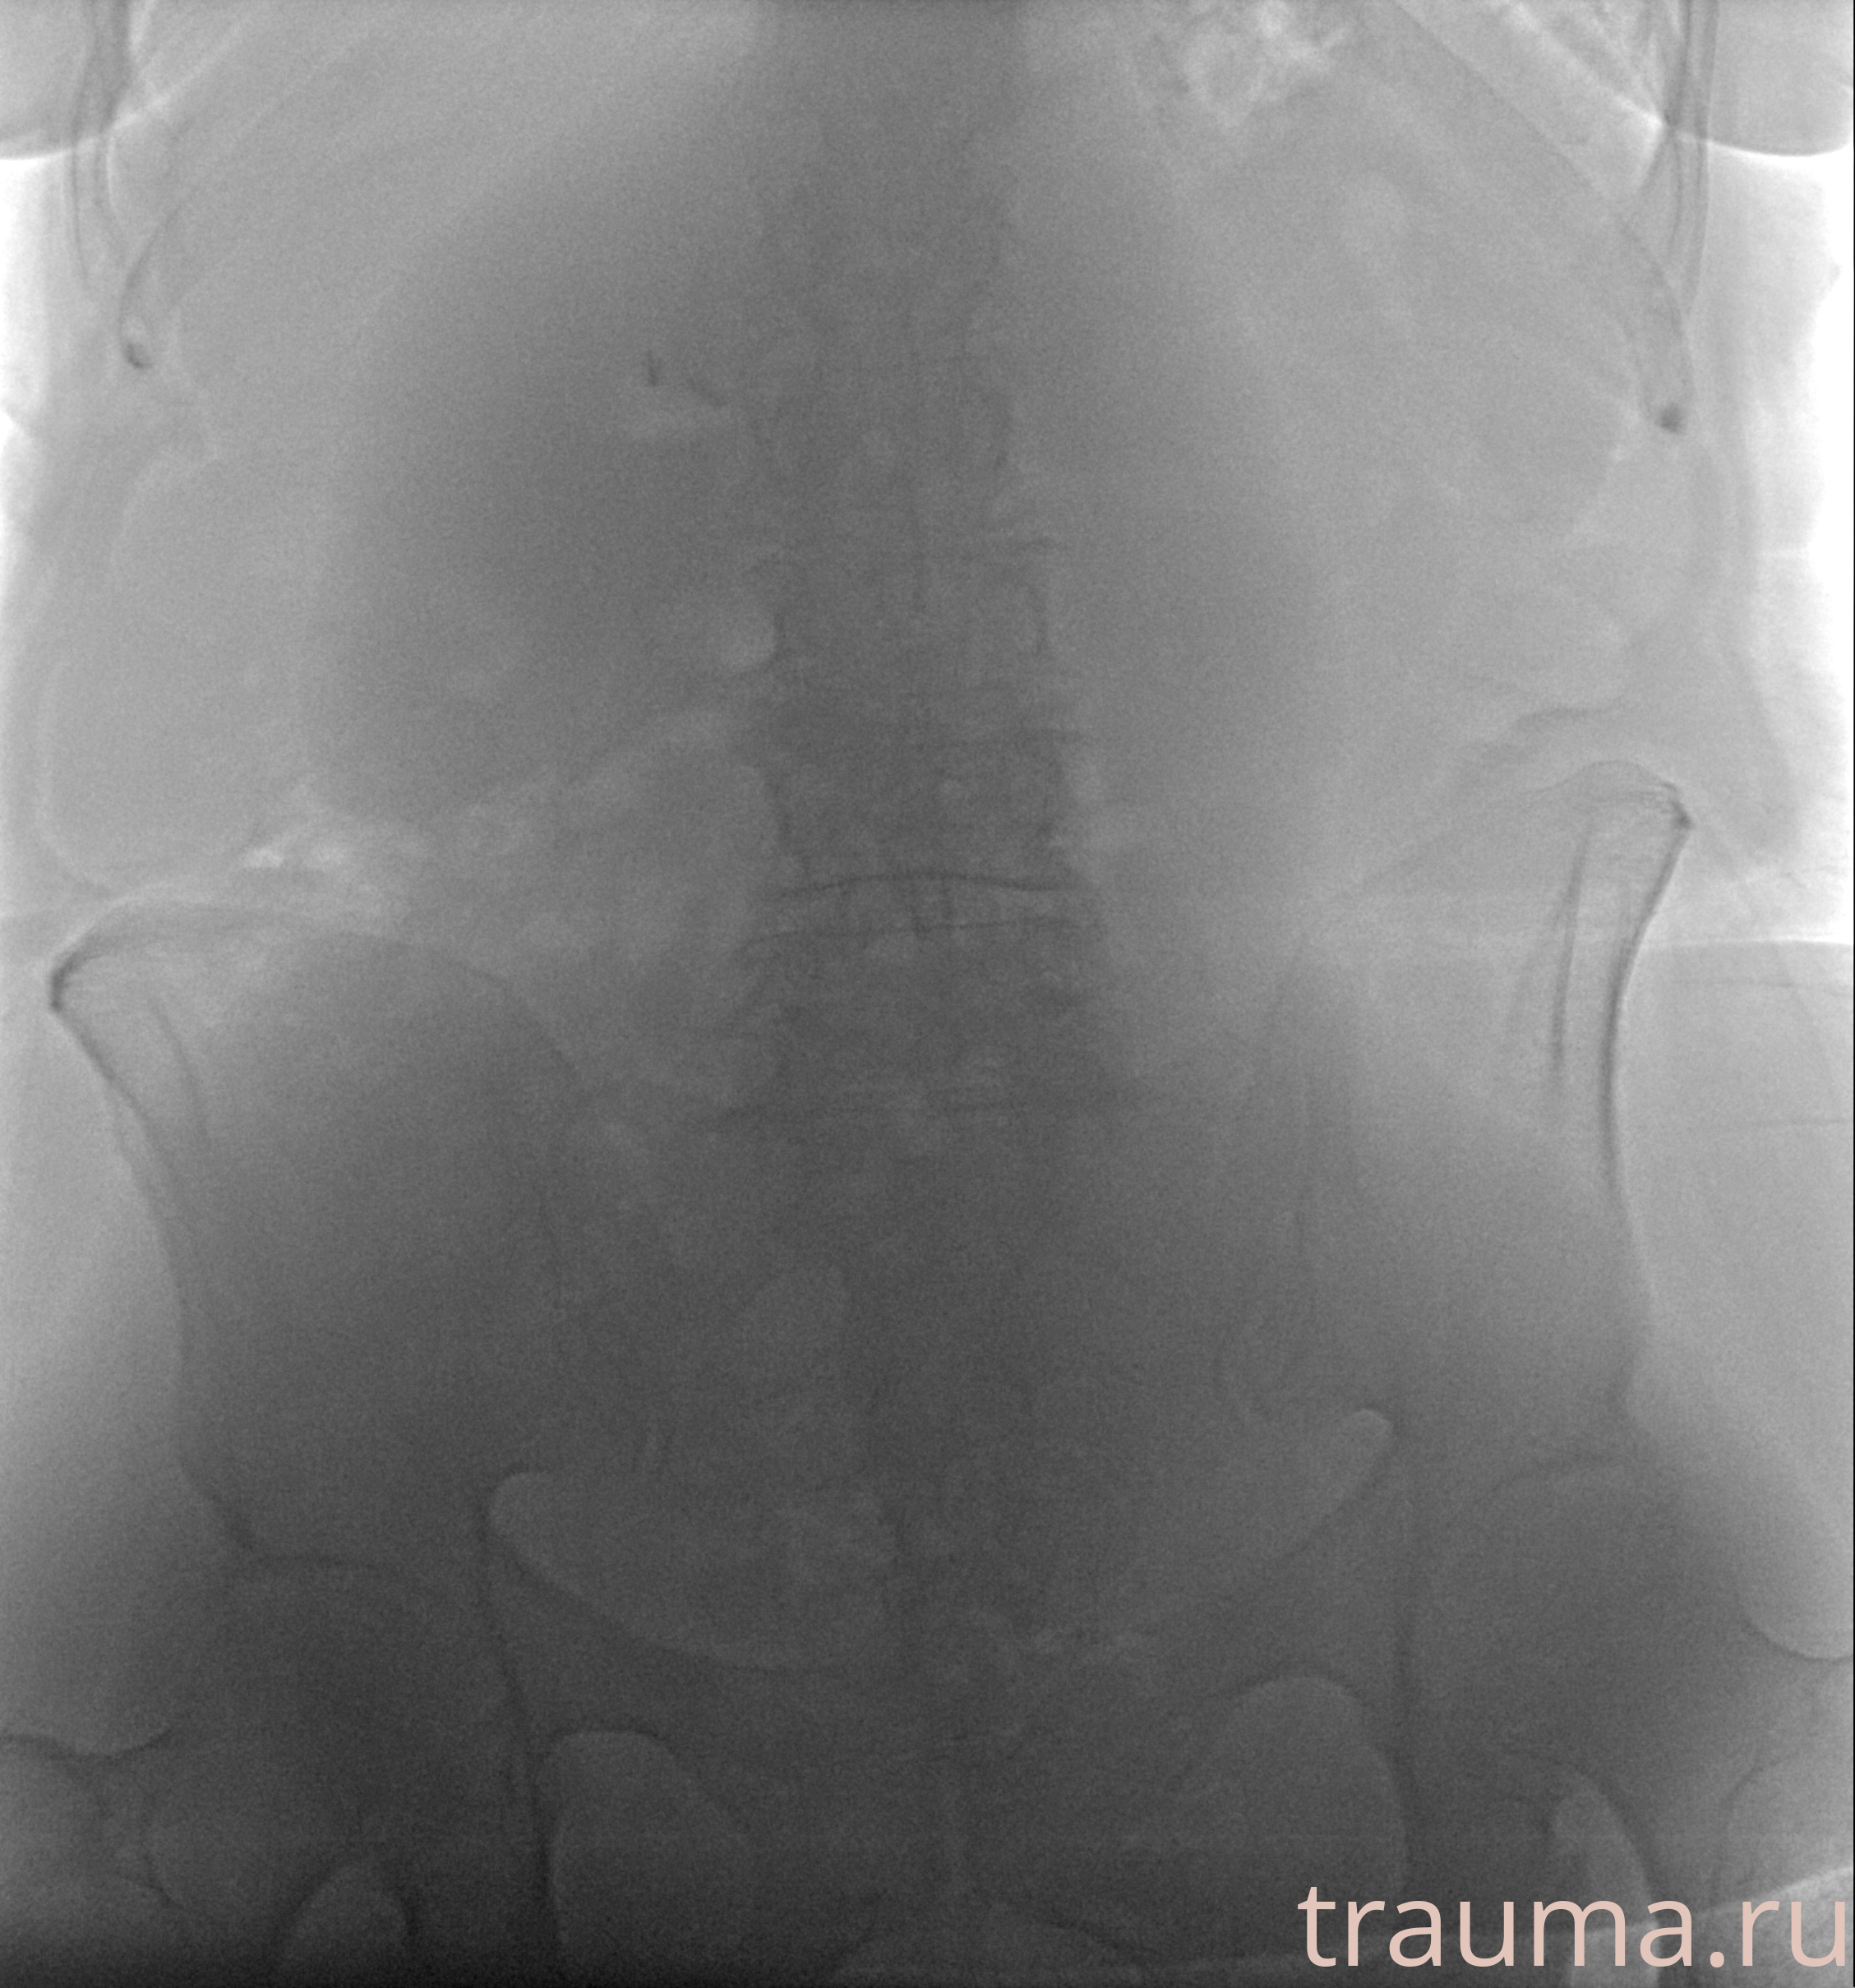

Рентген на дому: по вашему адресу приезжает врач-рентгенолог, травматолог-ортопед с мобильным рентгеновским аппаратом, проводит диагностику травмы или заболевания, делает необходимые рентгенограммы, дает рекомендации по дальнейшему лечению. Получить качественные снимки в домашних условиях возможно благодаря уникальной методике, разработанной МосРентген Центром для института  Склифосовского